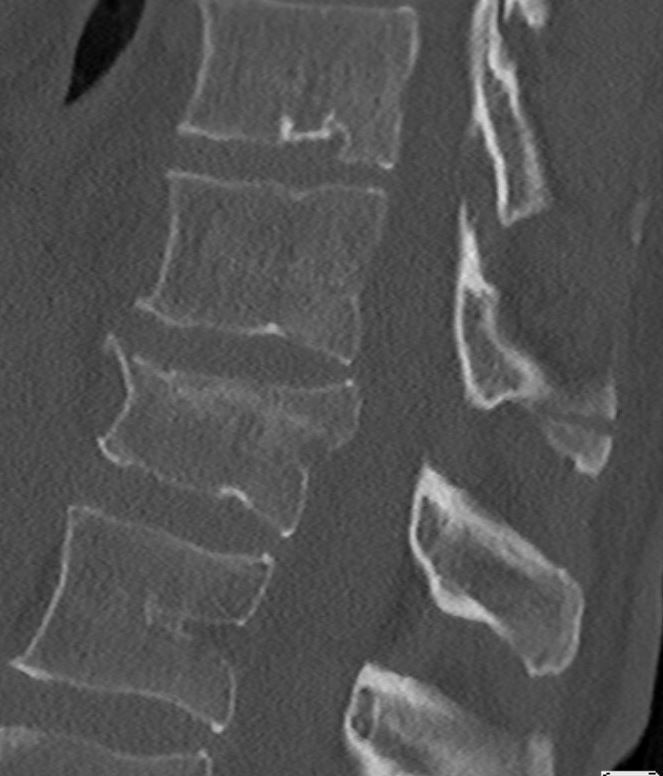

De breuk

Door een val of door een extreme buiging van de romp kan een breuk in 1 of meerdere rugwervels ontstaan. Afhankelijk van de plaats en het type breuk is de breuk stabiel of instabiel. Bij een stabiele breuk is alleen het wervellichaam gebroken en is het ruggenmerg niet in het gevaar. Bij een instabiele breuk is er wel kans dat het ruggenmerg beschadigd raakt of dat de breuk verder inzakt en daarmee de vorm van de wervelkolom verder verandert. Een stabiele breuk ontstaat meestal na een eenvoudige val, terwijl een instabiele breuk meestal na een val van hoogte of een verkeersongeval ontstaat. Om te bepalen of een breuk stabiel is, is er naast een Röntgen foto vaak een CT scan nodig. Ook wordt er vaak neurologisch onderzoek gedaan.

Afhankelijk van waar de breuk zich precies bevindt en of de breuk stabiel of instabiel is, zal uw behandeling bepaald worden. Stabiele breuken worden vaak met tijdelijke bedrust en later fysiotherapie behandeld, al dan niet in combinatie met een ondersteunend corset.